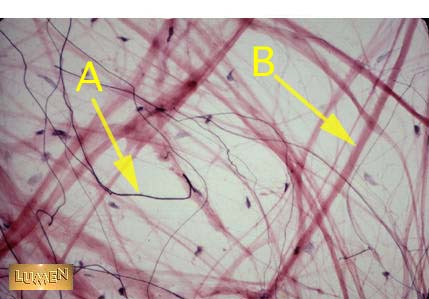

Identify the different tissues, 'A' and 'B'.

Answer A

Elastic fiber

Answer B

Collagen